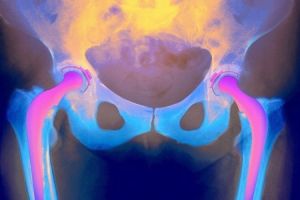

Рак тазобедренного сустава – опухоль, которая стремительно прогрессирует и метастазирует в ближайшие ткани и органы. Несмотря на редкую распространенность (1% от остальных видов раковых поражений организма), заболевание способно стать причиной летального исхода.

Опухоль тазобедренного сустава крайне опасна: она способна не выражаться в каких-либо симптомах вплоть до того, пока не даст метастазы. Чаще всего образование выявляют у детей, подростков и молодых людей до 20 лет.

Область тазобедренного сустава поражают опухоль Юинга, саркома и хондросаркома. Первая из них является наиболее опасной, относят ее к разновидности гигантоклеточной опухоли. При ее формировании пораженная область костных структур деформируется. Заболевание характеризуется выраженной клинической картиной уже на той стадии, когда опухоль дает метастазы.